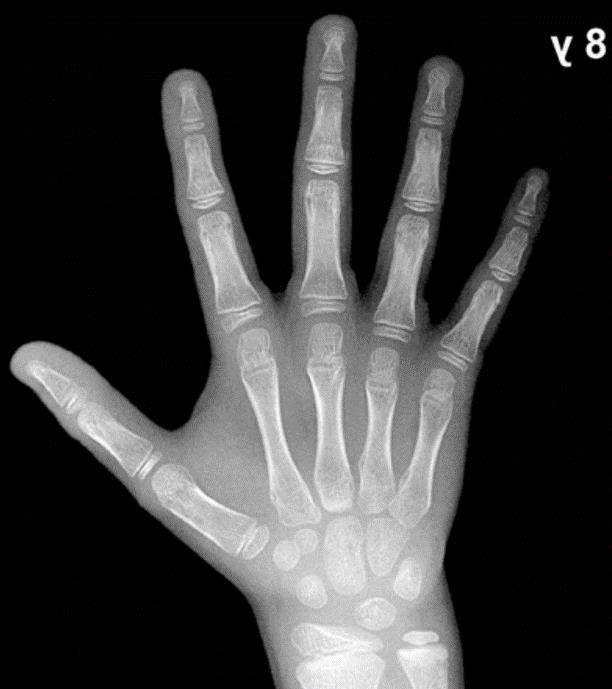

22 Figura 11. Carpograma de referencia de paciente masculino de 8 años de edad 23

Dado que el proyecto se encuentra enfocado a modelar el comportamiento de una mano de un menor de 8 años, se hace necesario determinar las medidas estándar de la mano, para ello, se emplea un carpograma de un niño de 8 años Esta imagen médica permite realizar la evaluación del crecimiento del paciente basado en las longitudes, espesores y separaciones entre los huesos de la mano. Por ello, se desarrollan atlas que indican los procedimientos de análisis de las dimensiones de la mano y exponen imágenes de referencia para determinadas edades. De “Hand Bone Age A Digital Atlas of Skeletal Maturity” se extrae el carpograma de un menor masculino de 8 años el cual puede observarse en la Figura 11. (Gilsanz & Ratib, 2005)

Figura 11. Carpograma de referencia de paciente masculino de 8 años de edad

Fuente: (Gilsanz & Ratib, 2005)

Teniéndose el carpograma de referencia, se importa dicha imagen a SolidWorks, con el fin de realizar el análisis de dimensiones correspondiente. Primero se determinan los puntos de análisis para cada hueso de la mano, acorde a las recomendaciones dadas en “Hand Bone Age A Digital Atlas of Skeletal Maturity”, obteniéndose una imagen con puntos de referencia (Figura 12).